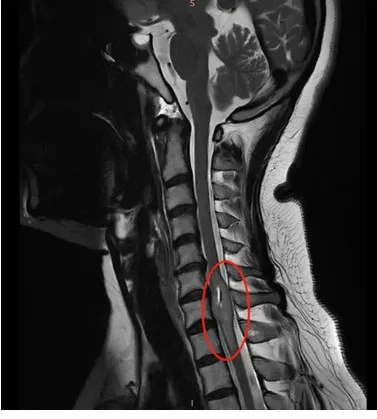

那位骨科医生经验丰富,听完我的描述,他表情严肃地建议我:“你需要拍一个核磁共振(MRI)。”我听从了建议。结果出来后,医生看着片子的表情让我心头一紧。他告诉我,我的脊髓里可能长了个肿瘤。那一刻,我完全懵了。肿瘤?我从没想过会这么严重,更没想到它会压迫那么多重要的神经。

为了确诊,我当天又做了增强核磁。中午12点,报告就出来了,我拿到了那个陌生的疾病名称:脊髓髓内肿瘤。从那一刻起,我的人生被彻底改变了。

肿瘤顺利全切